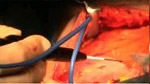

手術(shù)圖例-整形手術(shù)圖例

EE255使用圖例 Mid-facelife使用圖例

Mid-facelife使用圖例 Evisceration使用圖例

EE255使用圖例 Mid-facelife使用圖例

Mid-facelife使用圖例 Evisceration使用圖例